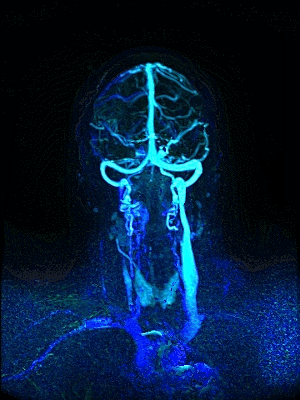

Perfusion MRI를 이용한 측부혈류영상

측부혈류영상과 동시 생성하는

동맥영상(Arteriography), 정맥영상(Venography), 역동적 혈관영상(Dynamic Angiography)

추가 촬영없이 측부혈류영상과 동시에 생성하는 세계최초 딥클루의 원천 기술

Simultaneous Vascular imaging

3D 동정맥영상

3D 동맥영상

3D 정맥영상

4D 혈관영상